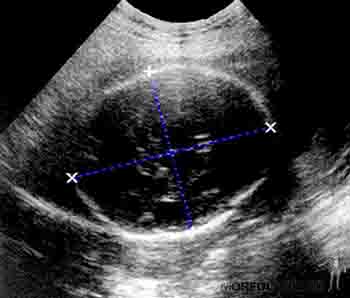

Durante el tercer mes, el rostro adquiere un aspecto más humano debido a que los ojos adoptan una posición más frontal y los pabellones auriculares, inicialmente colocados en la zona cervical, se ubican en la región lateral de la cabeza. A esta edad gestacional, los párpados están fusionados, aparecen los centros de osificación en los huesos largos y en la base del cráneo. Hacia fines del tercer mes los genitales han alcanzado un desarrollo suficiente como para poder definir el sexo del feto mediante ecografía. En este período es posible determinar ecográficamente el diámetro biparietal, dato que servirá de referencia para hacer el seguimiento del desarrollo fetal. La pared anterolateral del abdomen ha crecido lo suficiente como para incorporar en la cavidad abdominal las asas intestinales, reduciéndose así la hernia umbilical fisiológica (Figura 2-19).

Figura 2-19